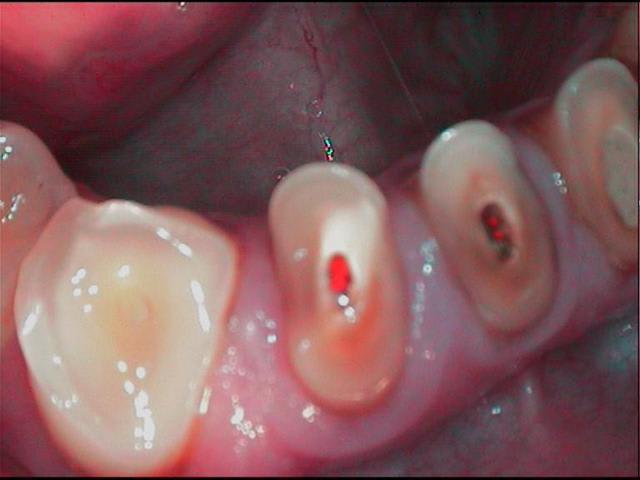

Initial abrasion vt1yph - Eugenol

Cavites fksl8t - Eugenol